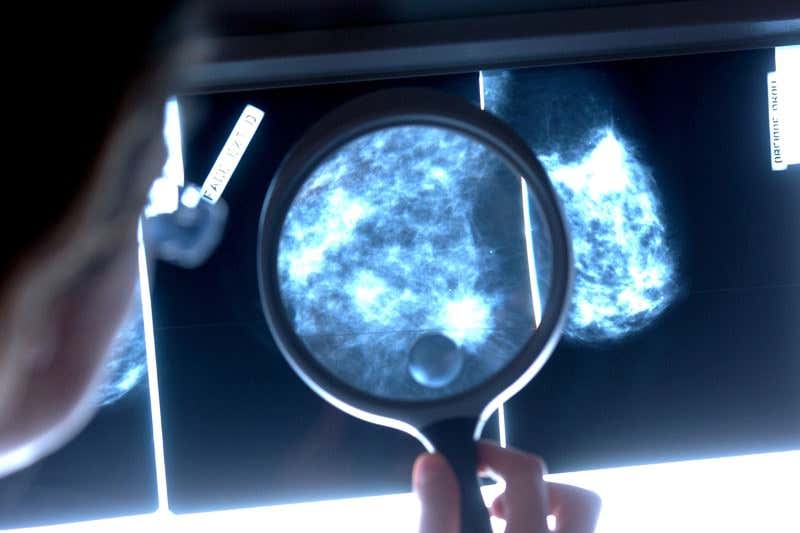

Not as tough as it looks (Image: Garo/Phanie/Rex)

Breast cancer is the second most common form of the disease. About 85 per cent of breast cancer tumours rely on the hormones progesterone or oestrogen to grow, or else on a protein called HER2. That makes them relatively easy to treat: block those chemicals and the cancer will usually stop growing.

But the other 15 per cent of tumours are what is called triple negative breast cancer, meaning that they don’t need either of the two hormones or HER2 to grow.